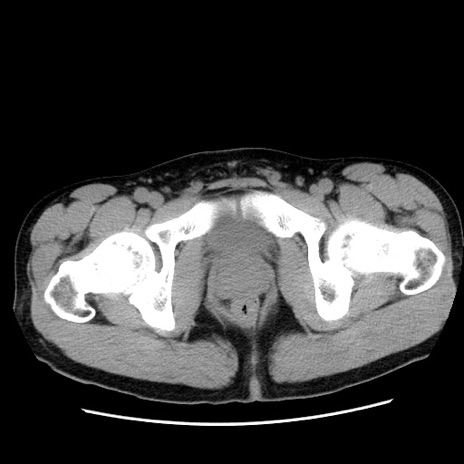

症例36(横断像)

【症例】20歳代 男性

【主訴】心窩部痛

【現病歴】今朝より上腹部痛あり。一旦軽快していたが再度出現したため救急要請。昨日夕に白身の魚を含む刺身を食べた。

【身体所見】BP 136/89mmHg、HR 74/min、BT 37.0℃、腹部:膨満、軟、心窩部に圧痛あり。反跳痛なし、筋性防御なし、腸雑音やや亢進あり。

【データ】WBC 17700、CRP 0.48